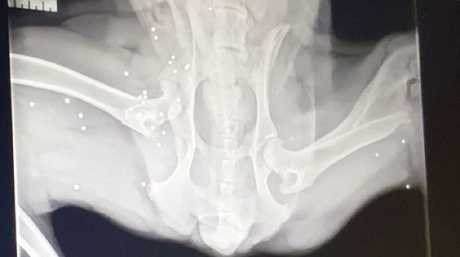

A surgical pelvic fracture in a cat

Play this video

16 Dec 2019

(Duration 04:12)